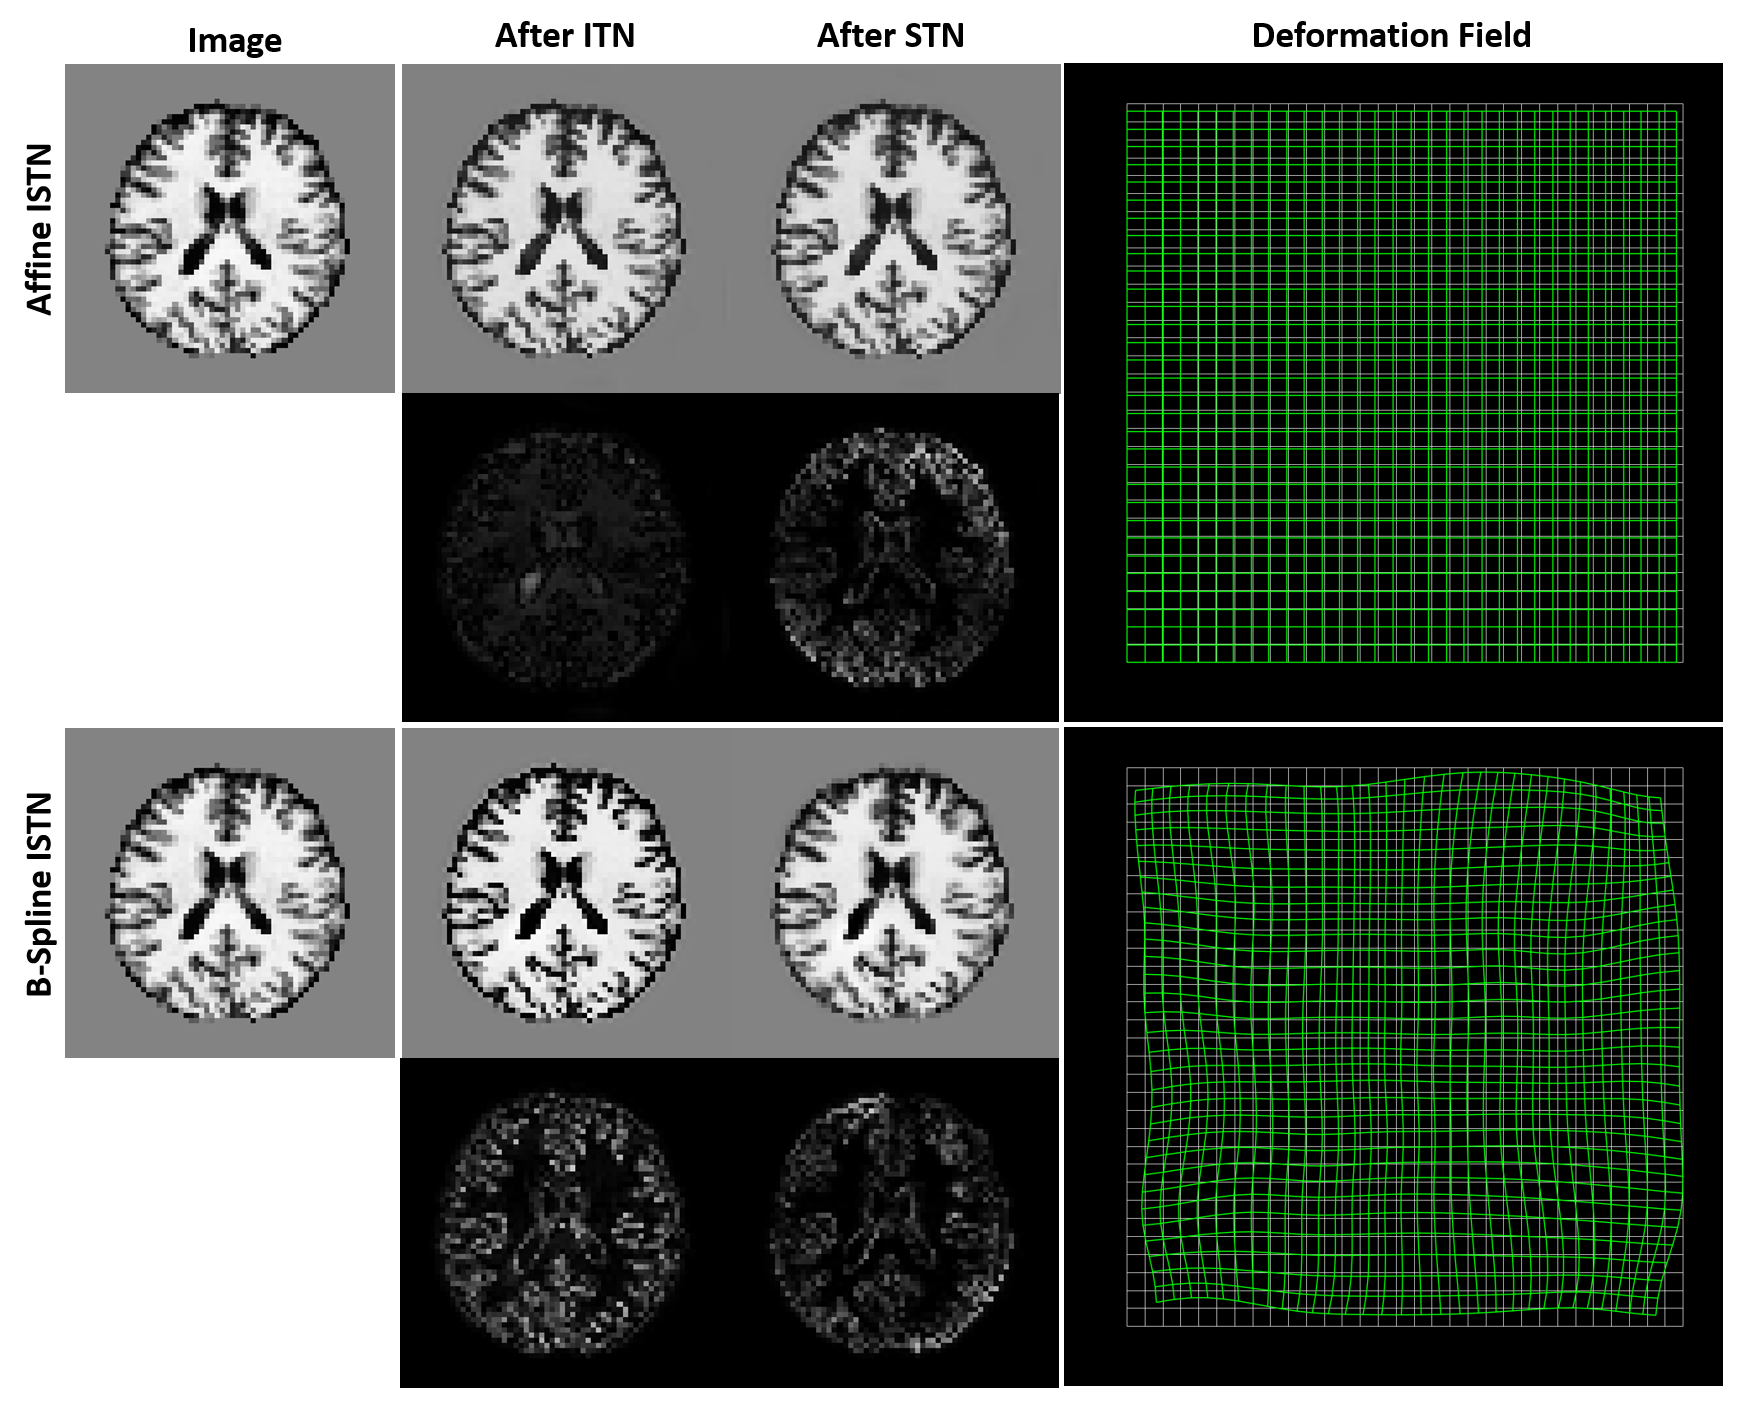

Refer to caption

Figure 3: The original image (left) passes through the ISTN. The transformations applied by the ITN and subsequently by the STN are visualized by showing difference images. The transformation applied by the STN can also be visualized as a spatial deformation field (right). This is shown for the Affine (top) and B-Spline (bottom) STNs.